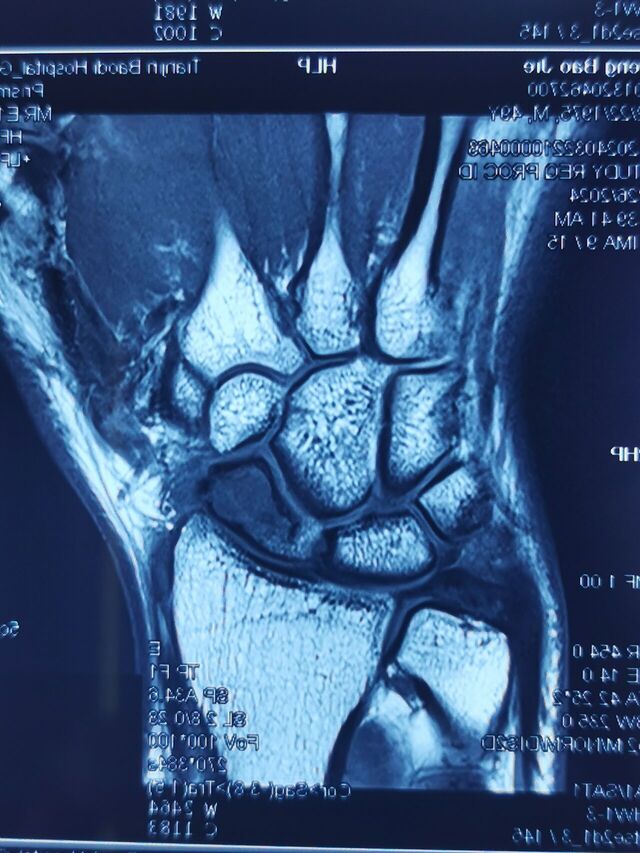

腕关节骨性关节炎

SLAC分期:

I期,舟骨窝局限性关节炎始于桡骨茎突

II期,发展到近端舟骨窝

III期,进而出现头月关节炎

IV期,全腕关节炎

该病例需要做CT重建

判断腕关节骨性关节炎分期

根据分期决定具体术式